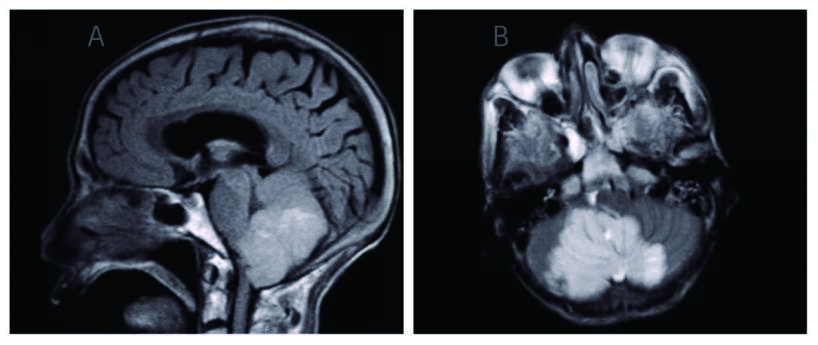

1 资料与方法患者男,70岁,农民,入院前3 d受凉后出现咳嗽,为阵发性干咳、无痰,伴胸闷、气喘,平卧及活动时加重,发热,体温最高37.7 ℃,热型未监测,无畏冷、寒战;当地医院胸部X线平片示左侧胸腔积液、左侧肺炎,予以“头孢噻肟”抗感染治疗无效,于2015年9月29日转来厦门大学附属第一医院。既往慢性支气管炎病史20余年,吸烟史50年×40支/d。入院时查体:T 37.6 ℃,P 106次/min,R 26次/min,BP 118/72 mmHg,SPO2 91%,神志清楚,反应迟钝,有时答非所问,呼吸较急促,气管轻度右偏;左侧胸部呼吸运动减弱,语颤消失,叩诊呈浊音,呼吸音减弱,右肺散在哮鸣音;心界不清,心率106次/min,节律规整,各瓣膜区未闻及杂音。入院后观察患者热型为不规则低热,查血尿粪常规、肝肾功能、肿瘤标志物等正常,降钙素原0.826 ng/mL,结核抗体及结核菌素实验阴性。血气分析:氧分压6.63 kPa,二氧化碳分压正常,无酸碱失衡表现。胸部CT示,双肺多发感染,左侧大量胸腔积液;右肺局限性肺大泡,肺气肿(图 1)。入院后给予莫西沙星抗感染,胸腔穿刺引流出大量淡红色稍混浊胸水,无臭味,每日引流量300~600 mL;胸水常规:李凡他试验阳性,蛋白48.6 g/L,有核细胞数1 520×106/L,比重1.021。患者仍有反复低热,热峰及持续时间稍改善。入院后10 d胸水培养结果回报为星型奴卡菌感染(图 3、4),抗生素更换为TMP-SMX 0.96 g/12 h联合红霉素0.25 g/8 h治疗,体温逐渐下降至正常,咳嗽、气喘症状缓解,胸水引流量逐渐减少至消失,PCT和血气分析结果恢复正常,胸部CT:左侧少量胸腔积液,伴积气(图 2)。于2015年10月25日出院,继续口服TMP-SMX片及红霉素片治疗,定期随诊。患者感觉恢复良好在出院后1个月左右自行停药,3个月后因右侧肢体无力再诊我院,颅脑MRI提示:大面积小脑梗死,脑疝并幕上脑积水(图 5),再诊时未再复查胸部CT,2 d后因呼吸循环衰竭死亡,家属未同意尸检。

| 图 5 大面积小脑梗死伴脑疝形成(A:矢状面; B:水平面) |